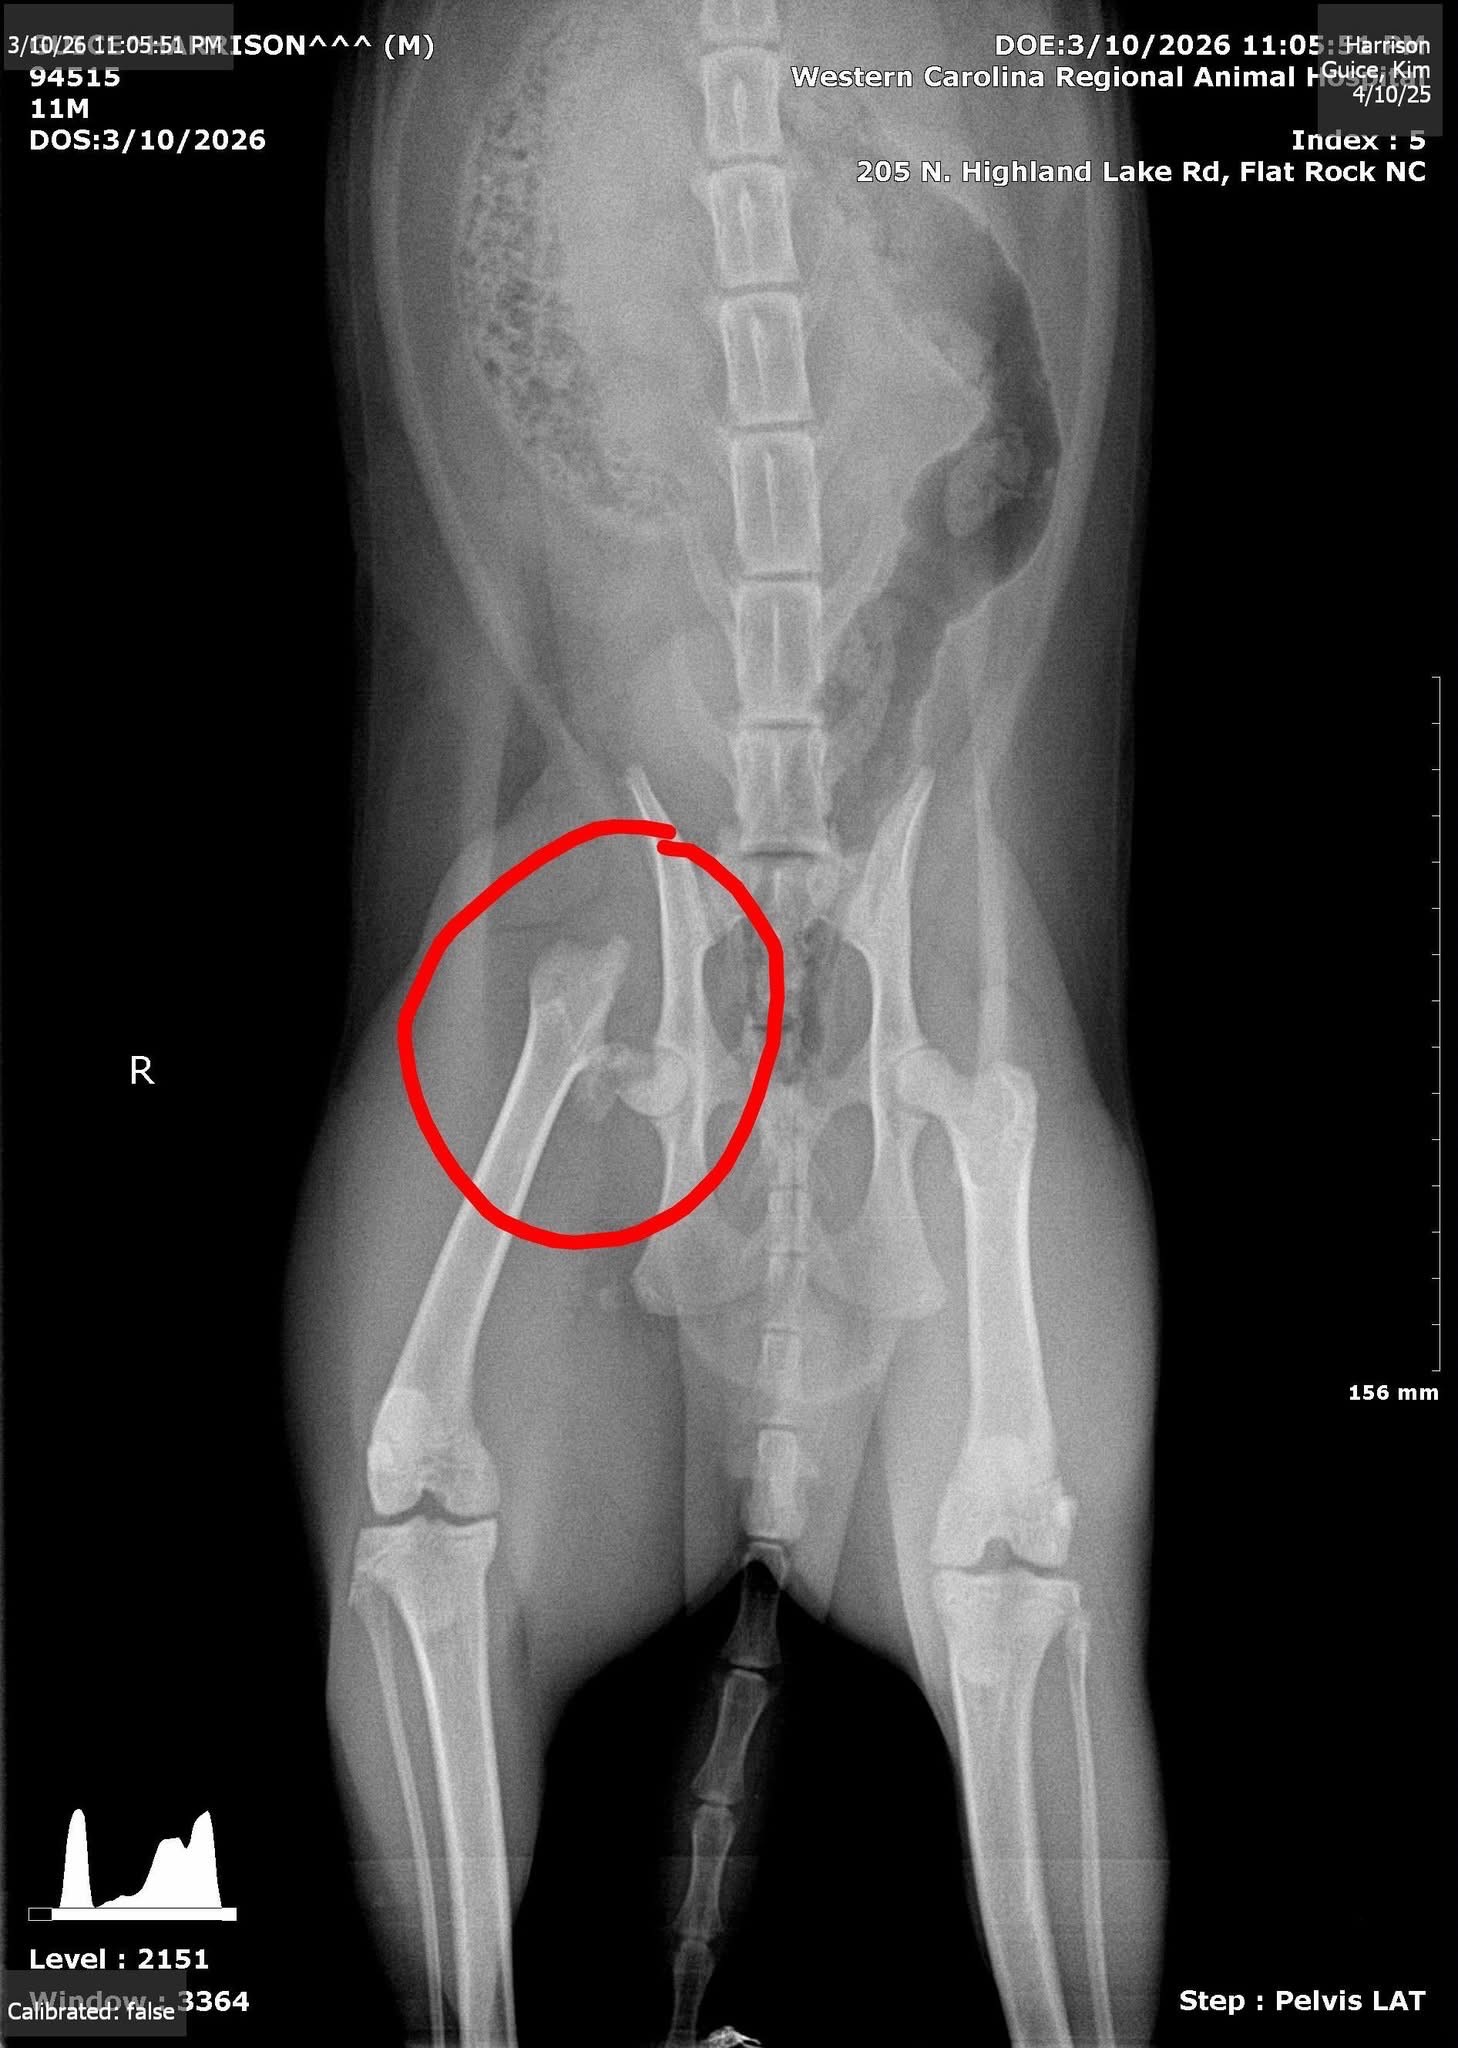

Harrison is an active, happy go lucky, and sweet natured boy who has always brought so much joy into our lives. Recently, Harrison suffered a broken femur, and it has been heartbreaking to see him in pain and unable to move around like he used to. He means the world to us, and seeing him struggle has been incredibly difficult for all of us.